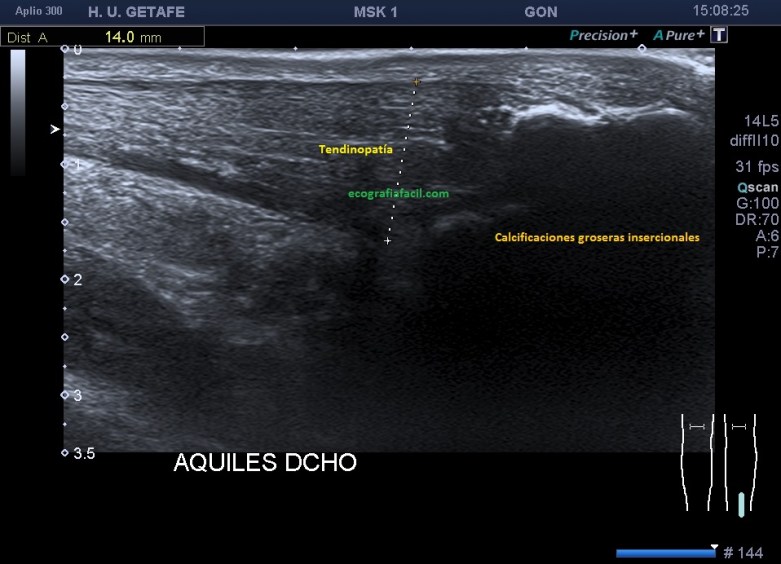

Ambas apariencias de las calcificaciones suelen verse acompañadas de tendinopatías, como muy puedes ver en la imagen 8 donde se demuestra un aumento del vientre del tendón marcado por la línea rosa, y como hemos dicho anteriormente, comos a unos 5 cms de la inserción.

Podemos encontrar calcificaciones muy groseras, insercionales y no insercionales, con tendinopatía asociada, como ves en la imagen 10.